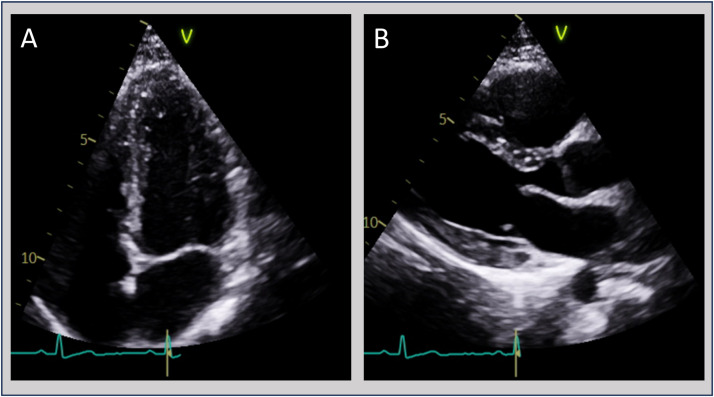

急性心肌炎是心肌的一种炎症,最常见的是由病毒感染引起的。细菌性心肌炎,特别是由于非伤寒沙门氏菌(NTS),是非常罕见的免疫正常的个体。我们报告一例罕见的沙门氏菌胃肠炎继发急性心肌炎病例,患者为23岁女性,其特征是心脏生物标志物升高,肠道沙门氏菌粪便培养阳性,心电图改变,心脏磁共振成像证实。治疗是保守的抗炎单药治疗,没有抗生素治疗,导致临床完全恢复,症状缓解,心脏生物标志物正常化。这个病例强调了一个罕见的nts相关心肌炎的表现,并建议保守管理可能足以在选定的病例。它强调了在急性心肌炎的鉴别诊断中考虑包括NTS在内的细菌性病原体的重要性,即使在免疫功能正常的患者中也是如此,并强调了多模式成像和个体化治疗策略在细菌性心肌炎中取得良好结果的效用。

Acute myocarditis is an inflammatory condition of the heart muscle, most commonly caused by viral infections. Bacterial myocarditis, particularly due to non-typhoidal Salmonella (NTS), is exceptionally uncommon in immunocompetent individuals. We report a rare case of acute myocarditis secondary to Salmonella gastroenteritis in a woman in her early 20s, characterised by elevated cardiac biomarkers, positive stool cultures for Salmonella enterica, electrocardiographic changes and confirmatory cardiac magnetic resonance imaging. Management was conservative with anti-inflammatory monotherapy without antibiotic treatment, resulting in full clinical recovery with resolution of symptoms and normalisation of cardiac biomarkers. This case highlights a rare presentation of NTS-associated myocarditis and suggests that conservative management may be sufficient in selected cases. It underscores the importance of considering bacterial pathogens, including NTS, in the differential diagnosis of acute myocarditis, even in immunocompetent patients, and highlights the utility of multimodal imaging and individualised management strategies in achieving favourable outcomes in bacterial myocarditis.